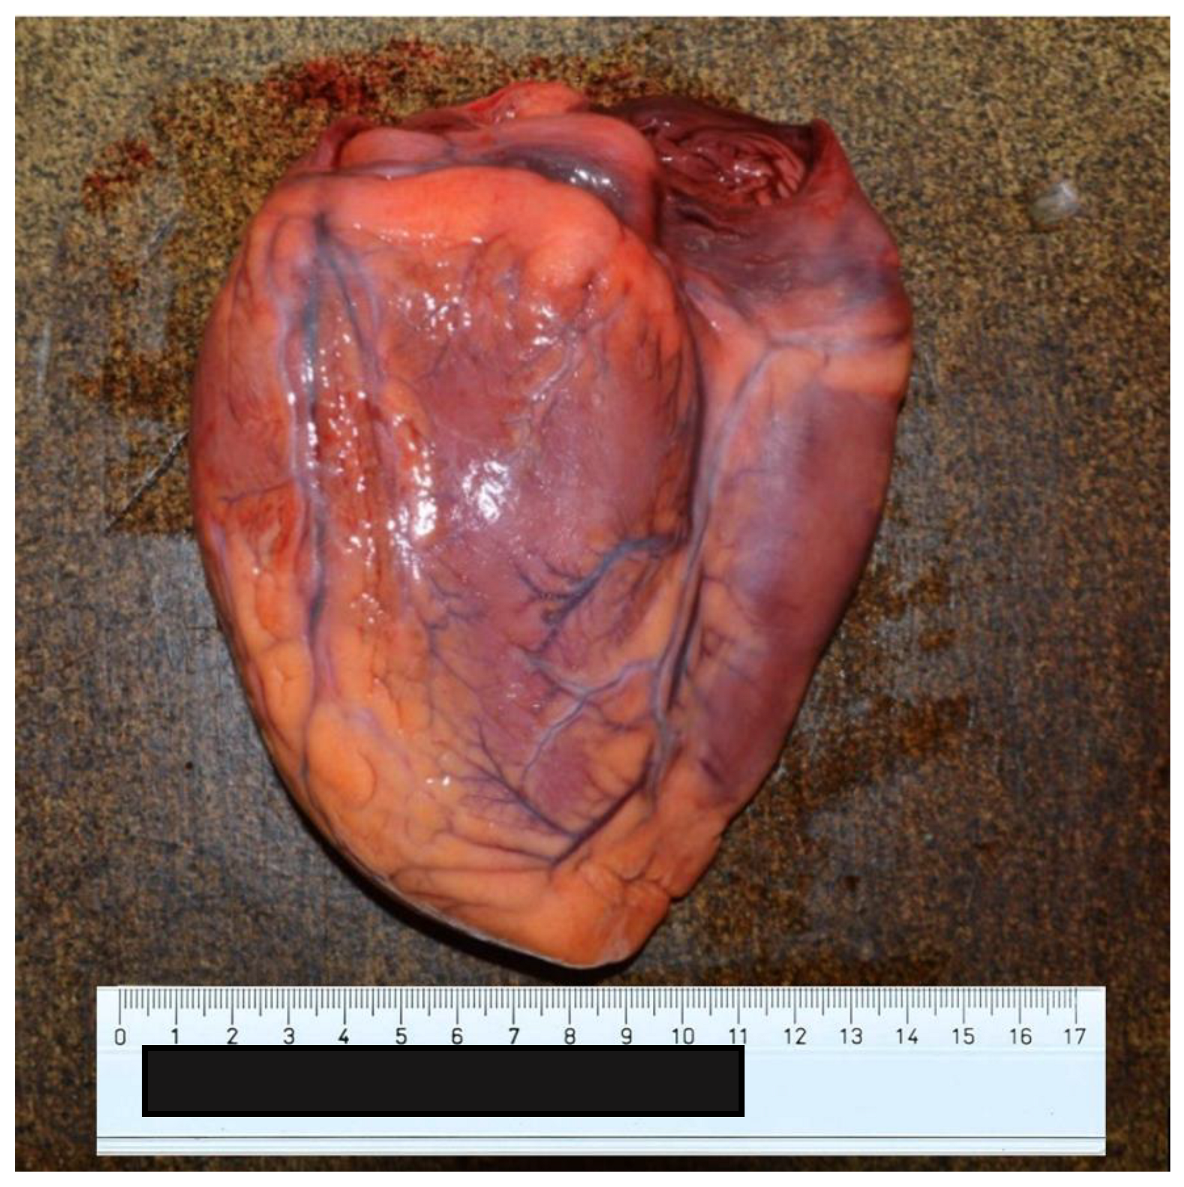

2. Case Presentation